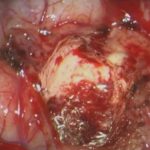

術中写真

No.’25_45 摘出 前

No.’25_45  摘出 中